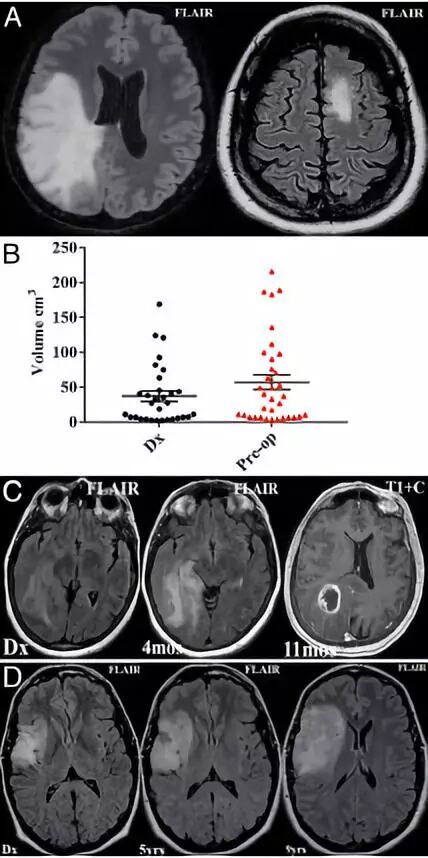

3. 偶发弥漫浸润性低级别胶质瘤的外科治疗

Surgical management of incidentally discovered diffusely infiltrating low-grade glioma.

PMID: 28984519 DOI: 10.3171/2017.3.JNS17159

随着医学成像技术的大量增加,偶发的无症状弥漫浸润性低级别胶质瘤(low-grade gliomas, LGGs)的诊断越来越常见,但这些病变的治疗至今仍有争议。本研究对接受手术治疗的偶发性LGGs患者的临床特点和手术预后进行回顾性分析。501例成人LGG患者中34例(6.8%)为偶然发现肿瘤。34例患者中,其中4例在影像学上发现肿瘤后进行了首次活检;有5例患者选择立即切除;其余病例采用“观察和等待”疗法,仅在出现疾病进展的影像学或临床证据后才进行干预。34例患者的平均随访时间为5年。

结果显示,12例(35.3%)出现病情进展,平均进展时间为43.8个月(3~105个月)。恶性进展5例(14.7%),死亡4例(11.8%)。少突胶质细胞瘤16例(47%),星形细胞瘤15例(44%)。IDH 1基因突变25例(74%),存活时间较长。仅2例有轻度手术相关并发症,16例(47%)在发病过程中发生癫痫。该研究结果表明,对于偶发的无症状弥漫浸润性LGGs,手术治疗可显著改善患者预后,建议早期手术治疗。